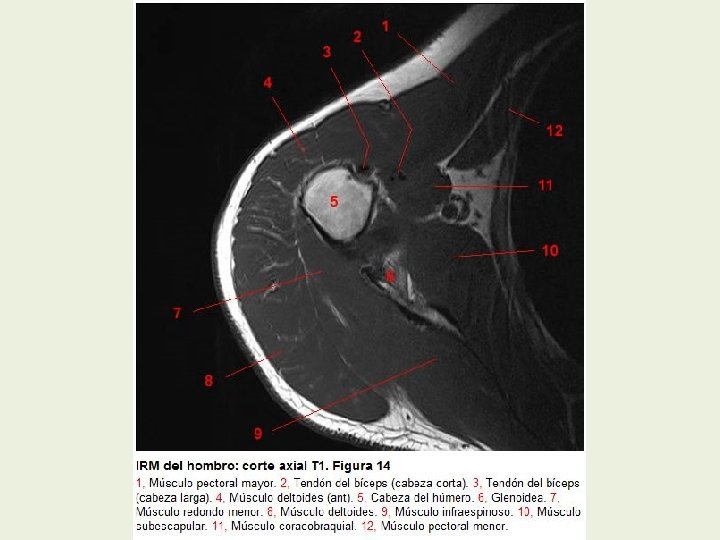

Hombro Cortes axiales RMN